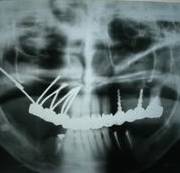

考古研究發(fā)現(xiàn),古埃及宮庭婦女就有采用骨內(nèi)種植動物牙和象牙雕刻的人造牙的記載,出土的人類頜骨化石中還發(fā)現(xiàn)鑲有寶石或黃金雕成牙體形狀的植入物,它是牙種植體的原始雛形,最早可以追溯到公元前6000年。 中國有記載的種牙歷史比較遲 約800多年前 陸游:“近聞有醫(yī)以補(bǔ)墜齒為業(yè)者。” 800多年前,我國宋代樓鑰所著的《玫瑰集》中,也記載著了種牙。 宋代的大文豪陸游,不僅是一位豪放詩人,也是一位醫(yī)學(xué)愛好者。在陸游的《歲晚幽興》中說:“卜冢治棺輸我快,染須種牙笑人癡。”更可貴的是,他還在詩后面加了自注:“近聞有醫(yī)以補(bǔ)墜齒為業(yè)者。” 為了口腔健康,世界各國的人們想盡了辦法! 公元前4世紀(jì),古希臘人就用人牙、動物牙、黃金和木材料來做人的假牙。 意大利西北部的伊特拉斯坎人在公元前700年就開始制作假牙,然后用金制箍條固定在鑲牙者口中。 在18世紀(jì)曾有從事“獵牙”者。1815年的滑鐵盧戰(zhàn)役留下的巨大牙齒資源,那一仗,拿破侖損失了3萬將士,英普等聯(lián)軍損失了2.3萬將士,這幾萬套“滑鐵盧牙齒”整整服務(wù)了歐美一代鑲假牙的人。 為了一顆好牙,人類的道德底線被擊穿了。 曙光與低谷 30年代至60年代的徘徊不前 1947年,M. formiggini以鉭絲錐形體植入口腔頜骨 1947年,M. formiggini以鉭絲錐形體植入口腔頜骨,成功地完成了義齒修復(fù),他被譽(yù)為口腔種植學(xué)的奠基人,口腔種植技術(shù)似乎看到了曙光。 但由于在五六十年代種植義齒的臨床應(yīng)用過分超前于基礎(chǔ)研究,造成種植高失敗率。1973年,國際衛(wèi)生研究所和美國牙醫(yī)學(xué)會的牙科材料委員會經(jīng)調(diào)查,對種植義齒持否定態(tài)度,牙種植由此一度跌入低谷。 終于找到開啟金色大門的鑰匙 1952-1982年,現(xiàn)代口腔種植學(xué)開啟 1952年,Br?nemark發(fā)現(xiàn)骨和純鈦能發(fā)生結(jié)合, 基礎(chǔ)研究的突破帶來了質(zhì)的飛躍 20世紀(jì)60年代,Br?nemark教授首次提出口腔植入體使用高純度的鈦金屬替代以往的黃金等貴金屬成為新的植入材料。他在動物實(shí)驗(yàn)中發(fā)現(xiàn),骨組織與植入的純鈦種植體結(jié)合得異常牢固,形成了一個完美的整體。 基于此項(xiàng)研究結(jié)果,Br?nemark教授創(chuàng)立了全新的骨結(jié)合理論:即人體活的骨組織與鈦種植體之間發(fā)生牢固、持久而直接的結(jié)合。該理論的確立在種植體領(lǐng)域掀起了革命性的變化。 在有記載的7000多年口腔種植歷史中,人類一直站在這扇厚重的金色大門前,束手無策。Br?nemark教授重于找到了開啟金色大門的鑰匙,人類正式步入現(xiàn)代口腔種植學(xué)的殿堂。 在這30年中 Br?nemark教授和他的團(tuán)隊(duì) 克服了無數(shù)的困難與質(zhì)疑 由于厚積了幾千年的失敗經(jīng)驗(yàn),物理學(xué)家和牙醫(yī)們思想已經(jīng)被牢牢固化。他們認(rèn)為非生物材料不可能融入活的生物組織——最初的炎癥和最終的排異是不可避免的,這個過程也會給病人帶來極大的痛苦。 Br?nemark教授的發(fā)現(xiàn)有悖“傳統(tǒng)智慧”,因此,即使在1965年Br?nemark教授為G?sta Larsson先生成功的進(jìn)行了鈦種植體種入,前方的路途依然漫長而坎坷。 現(xiàn)代口腔種植學(xué)的起源一方面來自骨結(jié)合理論的確立,另一方面還源于Br?nemark教授建立起的現(xiàn)代口腔種植標(biāo)準(zhǔn)化操作流程,他所著的《OSSEOINTEGRATED IMPLANTS》一書是現(xiàn)代口腔種植學(xué)的第一座里程碑。 在1982年多倫多召開的牙科種植大會上,Br?nemark教授向與會者展示了其團(tuán)隊(duì)在齒科種植體領(lǐng)域15年的工作成績。從骨結(jié)合理論的發(fā)現(xiàn)與應(yīng)用,到大量的、全新整理的科學(xué)實(shí)驗(yàn)數(shù)據(jù)以及世界第一例成功種植牙臨床病例,終于獲得了與會者廣泛的關(guān)注和認(rèn)可。 1982年多倫多召開的牙科種植大會 向Br?nemark教授和他的團(tuán)隊(duì)致敬! 在金色大道上高歌前行 Nobel Biocare 時代來了 1978年,諾貝爾工業(yè)集團(tuán)與Br?nemark教授開始合作,1981年Nobelpharma AB公司成立,1996年,公司更名為今天的Nobel Biocare公司。 一 Br?nemark System® Nobel Biocare經(jīng)久耐用的Br?nemark System®,G?sta Larsson先生使用了該系統(tǒng),運(yùn)行40年依舊穩(wěn)固如新。 二 NobelReplace® Tapered Replace Select™ Tapered NobelReplace® Tapered(諾保易配錐形)及Replace Select™ Tapered(易配精選錐形)模仿自然牙根的形狀,該設(shè)計(jì)在所有負(fù)重方案,包括即刻行使功能中,都能取得極高初始穩(wěn)定性。 更新、更領(lǐng)先的系統(tǒng) NobelReplace® CC (Conical Connection) NobelReplace® CC (Conical Connection)結(jié)合獨(dú)創(chuàng)的錐形種植體主體和緊密密封的錐形連接體,為您和您的患者提供了一種適用于所有適應(yīng)證的美齒解決方案。種植體主體可模擬自然牙根的形狀,旨在實(shí)現(xiàn)各種負(fù)重治療方案(包括 Immediate Function-即刻行使功能)的較高初期穩(wěn)定性。 NobelReplace® CC (Conical Connection)2011年全球上市(2015年中國上市)。 三 NobelActive® NobelActive®是具有劃時代意義的種植體。其體部及螺紋設(shè)計(jì)可以在植入時使進(jìn)行骨擠壓,即使在骨質(zhì)受損的情況下,也可以獲得很高的初始穩(wěn)定性。這使之成為即刻種植的理想之選。另外,頂部帶鉆刃的反向切割槽,可以調(diào)整種植體方向,以獲得最佳修復(fù)方向。 NobelActive®2008年全球上市(2012年中國上市)。 四 NobelSpeedy®系統(tǒng) NobelSpeedy®系統(tǒng)即使在軟質(zhì)骨中使用也有很高的初始穩(wěn)定性,操作高效省時,同時具有卓越的多功能性和享受修復(fù)靈活性,特別是在快速骨形成的愈合時期保持很高的穩(wěn)定性,確保長期成功。 All-on-4®治療概念由帶有外六角的NobelSpeedy®種植體發(fā)展而來。 什么是 All-on-4® 概念? 開發(fā) All-on-4 臨床解決方案的目的在于最大限度地利用可利用骨量并支持即刻負(fù)重。 四顆種植體支撐全口無牙頜: 2顆前牙種植體,直的 2顆后牙種植體,傾斜的 全口樹脂牙橋進(jìn)行即刻、臨時、固定修復(fù)與負(fù)重。 All-on-4®是NobelBiocare的注冊商標(biāo)